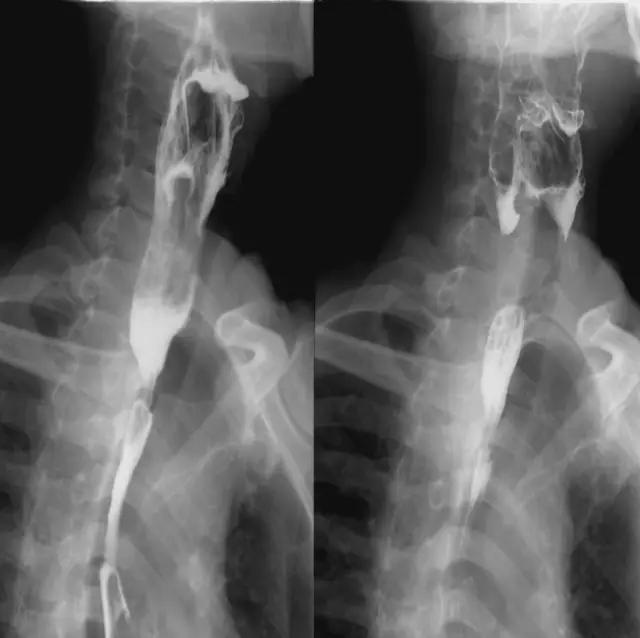

平片:侧位片观察喉部结构,正位片主要观察喉外伤和异物。

特殊检查:主要采用体层摄影,侧位体层以矢状面正中向两侧各0.5cm间距共摄3张,正位体层分别在平静呼吸、闭气及发“依”音照片,观察声带活动限度。